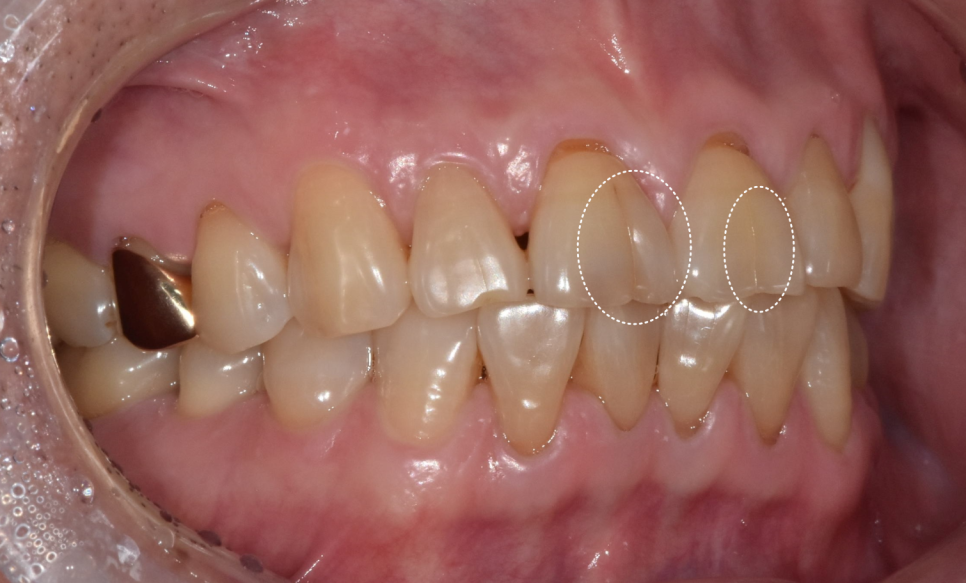

앞니 통증이 갑자기 심해져 내원하신 환자분의 사례입니다.

치아를 살펴보니 앞니 앞면 중앙에 금이 쭉 가 있었습니다.

치경부(치아와 잇몸 경계) 쪽엔 마모가 진행되어 뿌리 쪽이 파여있습니다.

250626 앞니 금 갔을 때, 방치하면 안 되는 진짜 이유 <파절 치료 사례>

특히 금이 더 깊게 간 오른쪽 앞니 통증을 호소하셨습니다.

자연치아를 최대한 보존하기 위해

처음부터 신경치료를 하지 않고

먼저 금이 간 감염된 부위만 제거한 뒤

남아있는 신경을 그대로 보존하는 방법을 선택했습니다.

신경을 보호하는 재료로 메우고 지켜보기로 했죠.